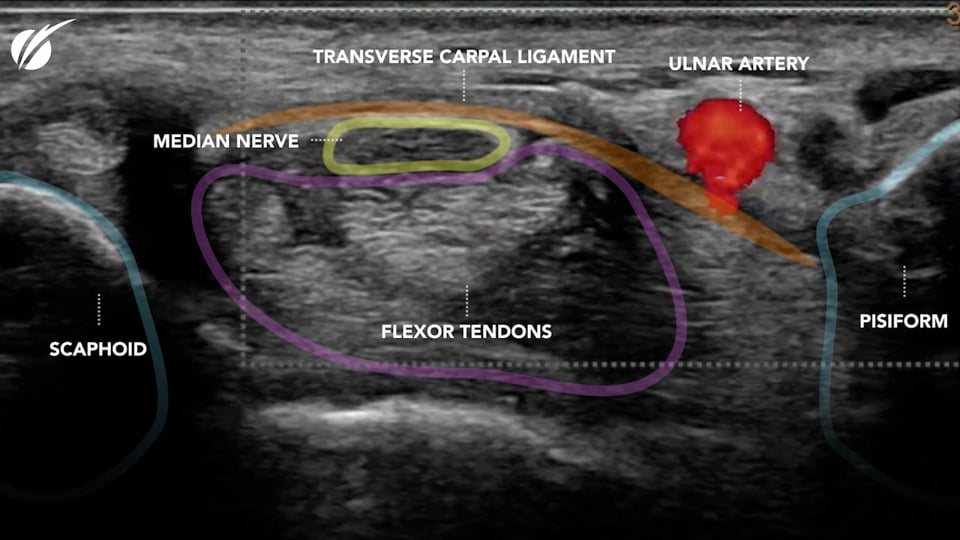

What makes this approach safer?

What makes this approach safer? Full Description